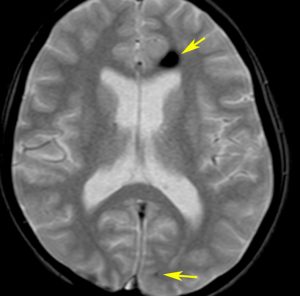

放射線誘発海綿状血管腫,微小静脈閉塞,血液漏出

- 放射線治療を受けた小児患者の4割以上に海綿状血管腫が発生したとの報告があります

- 長期観察をしていると実際に非常に高頻度にみます

- MTX メソトレキセートを使用していると発生頻度が増えます

- 海綿状血管腫は,放射線誘発2次腫瘍というよりも,放射線による脳内小血管損傷による血管障害として捉えた方がよいです

- T2スターというMRI画像で発見できます

- 低信号(黒いシミみたいなもの)として脳内たくさん見られることがあります

- これは血液の中の鉄分が脳に滲み込んだ形跡をみているものです

- だから,海綿状血管腫とは言わないで,blood leak(血液が漏れた痕跡)と読んだ方がいいものです

- 海綿状血管腫というと腫瘍みたいだからです

- 年月の経過とともに数が増加します

- 海綿状血管腫は発生しても何ら症状を呈することはありません

- 治療をせずに放置します

- まれに小さな脳出血を生じますが,経過を見れば血腫は自然に吸収されます

- またサイズが大きな皮質を侵す海綿状血管腫は症候性てんかんを生じることがあります

- とても大きなもの2から3cm以上くらいになると摘出を考えることもあります

- でもほとんど手術などしないでほっておきます

左から,33歳時,35歳時,39歳時の延髄出血です。11歳の時にジャーミノーマで全脳室照射を40グレイ受けました。ジャーミノーマは治ったのですが,延髄左側に海綿状血管腫が22年後に発生して,延髄出血を繰り返しました。もちろん手術などはしません。自然に吸収されてまた落ち着きます。